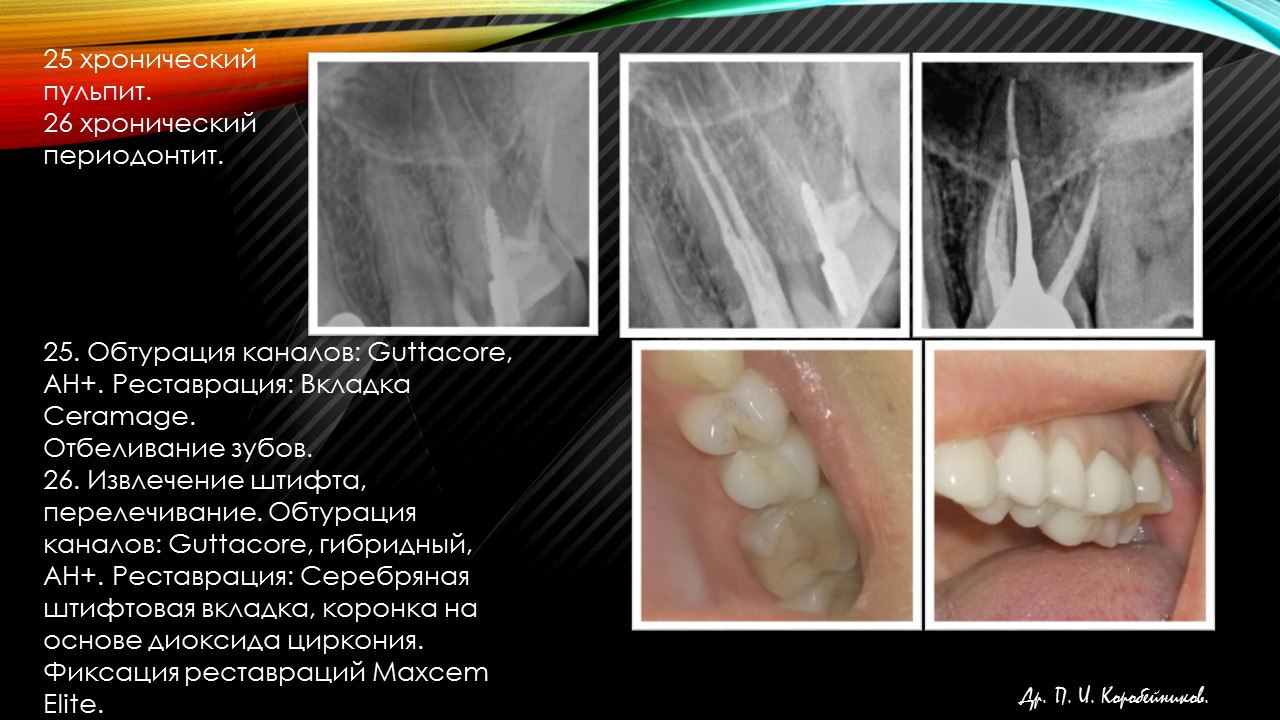

Стоматолог- эндодонт, стоматолог- терапевт, стоматолог- ортопед, стоматолог- хирург.

Работа с микроскопом, консультации и лечение пациентов, эндодонтия, терапия, ортопедия, хирургия(в небольшом объеме).